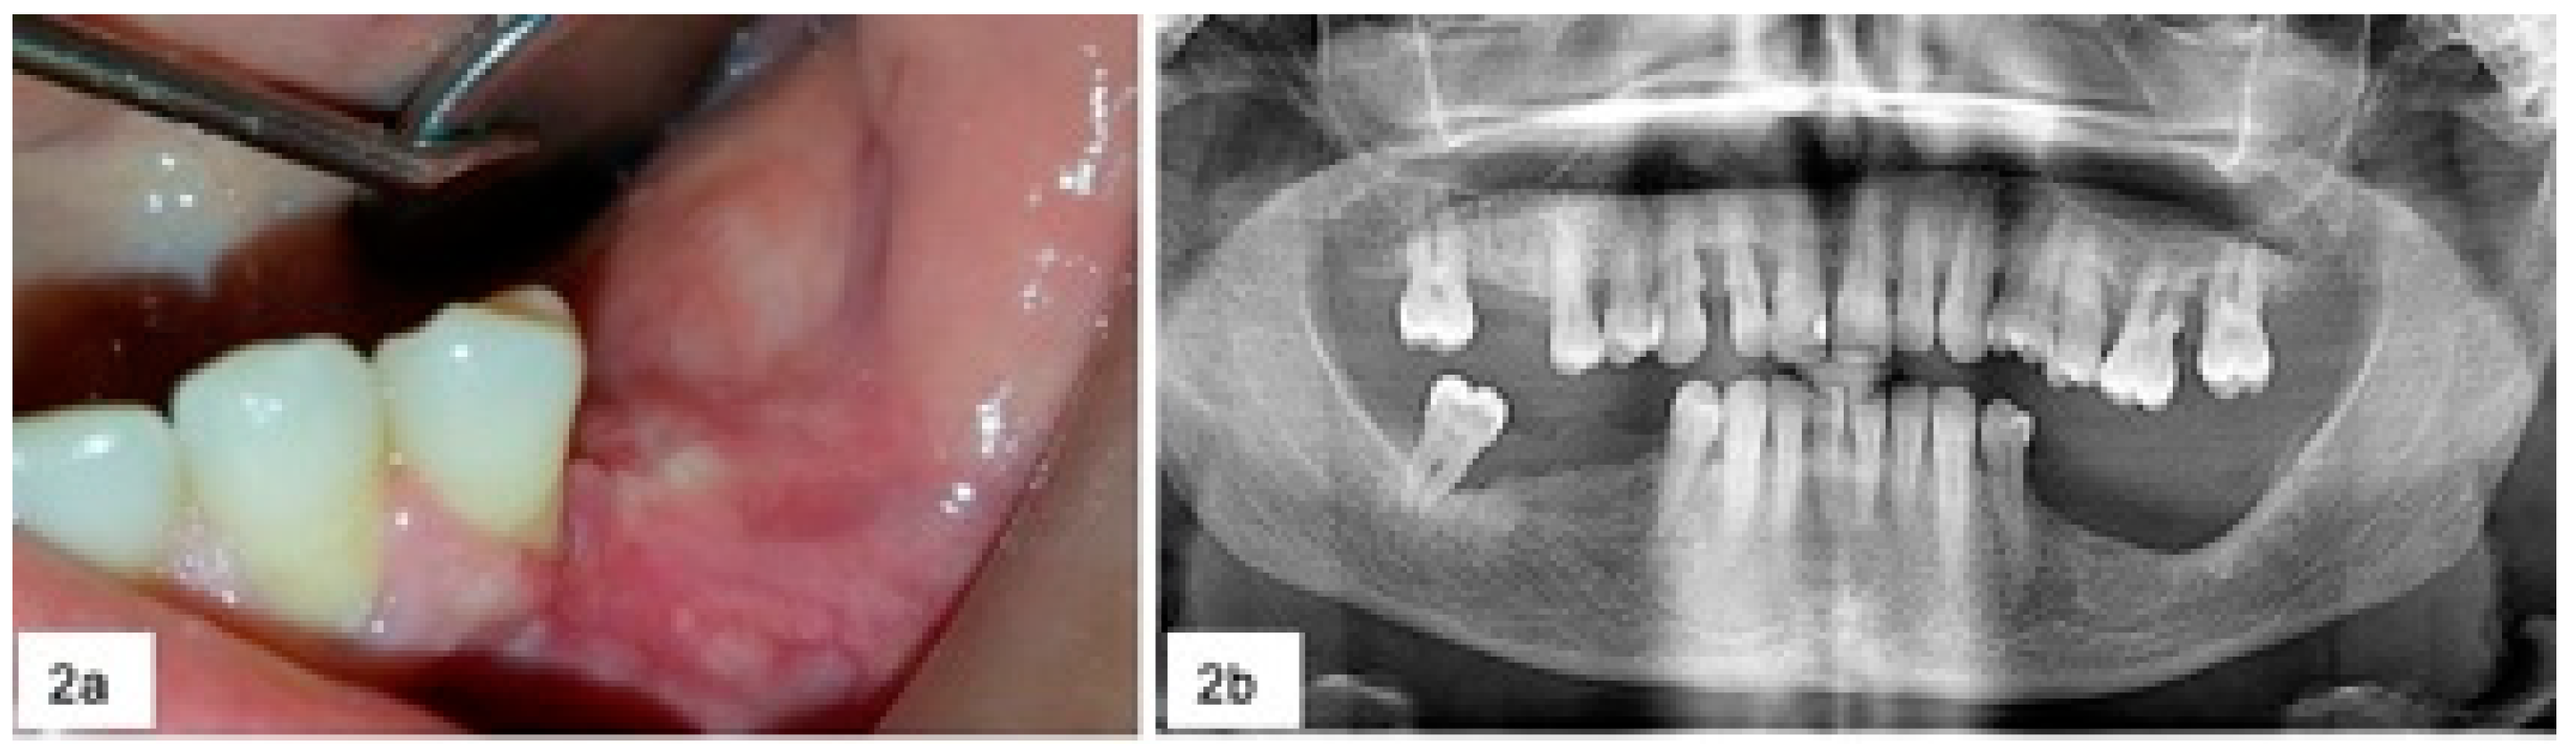

All the lesions were reddish-bluish, firm, painless and rapidly growing. Seventeen were sessile while 4 were peduncolated; 18 lesions were ulcerated and spontaneously bleeding (Figure 1). Clinical data of lesions were resumed in Table 1.

During surgery, in the five cases of severe horizontal bone loss, five teeth and one implant were removed (Figure 2) and abundant bleeding was noticed in 18 cases.

Figure 1. (a) Rapidly growing lesion in 3.6 region with severe horizontal bone loss and mobility of both 3.5 and 3.7 (b).